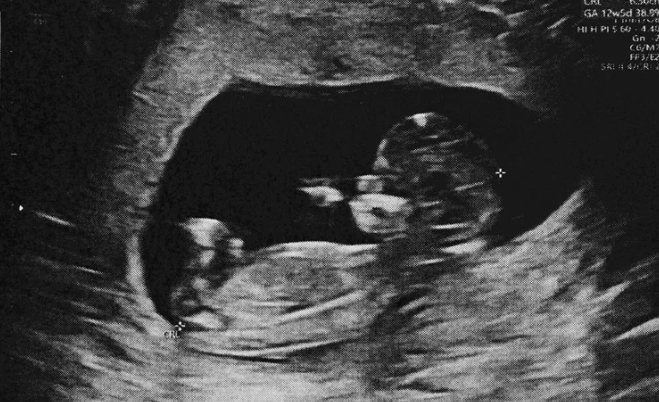

Ультразвуковое исследование является наиболее часто используемой технологией получения медицинских изображений. Важно отметить, что изображения, получаемые при ультразвуковой визуализации, зависят от квалификации и других характеристик как оператора, так и интерпретатора, что затрудняет клинически полезное моделирование DL.

Ультразвуковая визуализация плода имеет решающее значение для определения анатомии плода и наличия у него пороков развития. Учитывая высокую частоту врожденных аномалий почек и мочевыводящих путей (CAKUT), составляющую один случай из 500 живорожденных, включение ДЛ в пренатальный скрининг может позволить врачам диагностировать эти состояния на более ранних стадиях, что улучшит результаты лечения пациентов.

Для обучения в данном исследовании было использовано около 970 ультразвуковых изображений, которые включали в себя около 650 контрольных и 320 изображений с аномальной анатомией почек. В частности, около 260 изображений демонстрировали одностороннее расширение мочевых путей (UTD), а 64 - одностороннюю мультикистозную диспластическую почку (MCDK).